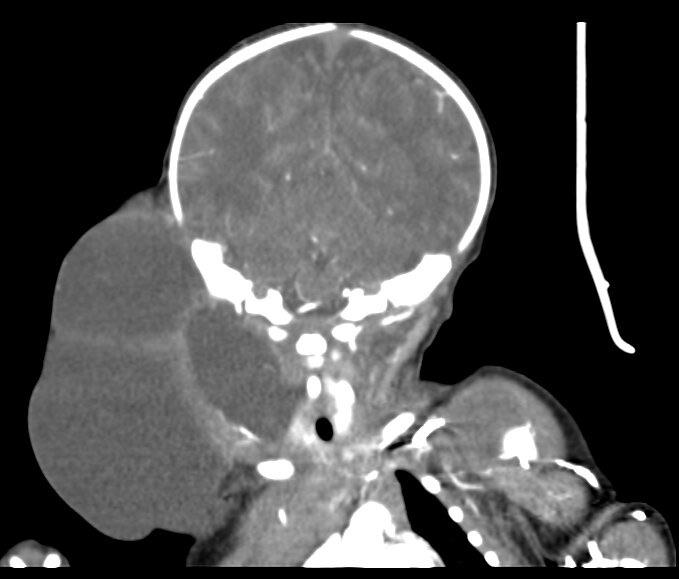

典型特征为沿疏松结缔组织间隙呈“爬行性”生长,大小不等,其形状与周围组织间隙相吻合,与周围肌肉或脂肪等组织结构分界清晰。邻近血管或肌肉有包饶或移位现象,范围可上达颌下间隙甚至颞部,下至纵膈,向外可达腋窝。CT上表现边界清楚、单囊或多囊、水样密度肿块、密度均匀,囊壁多菲薄或不能显示。单囊型主要表现为圆形或类圆形,而多囊型则呈现出不规则形,或可见囊内分隔呈网状轻度强化(图5B~C),增强囊壁及分隔轻度强化,囊内不强化。当伴有囊内出血时,可见囊内增高的片状密度影,可能出现“液-液平面”征像,上层液体为低密度,下层液体为血细胞沉积的缘故,呈高密度。

(B)CT显示右侧颈部约7.5*8.6*9.4cm均质、低密度囊状肿块,增强后未见强化,形态不规则,内部见条状分隔。